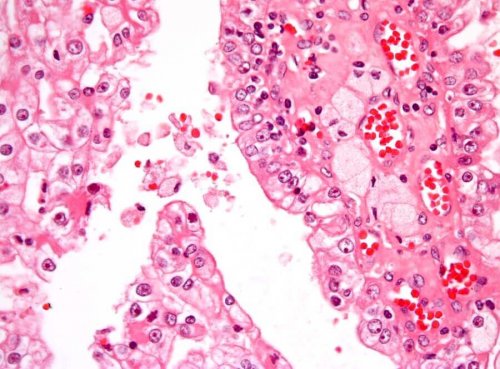

Uzmanın belirtmesi dâhilinde tümör biyopsisi gerçekleştirilebiliyor. Bu teknikte ise hücreler ya da dokular bir hastalık bilimleri uzmanı tarafından mikroskobik olarak incelenmek üzere bir iğne aracılığıyla parçalanıyor.